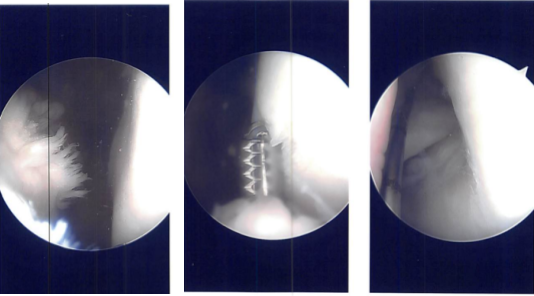

A plane was made between the popliteus and the gastrocnemius with the vessels behind. Sims speculum was used to retract the vessels posteriorly. Another scope was reintroduced on the lateral border and all-inside repair was done using FasT-Fix with a Nephew curved all-inside implant and sutures.

Three of them were put in the body posterior and medial to the popliteus muscle and one was put lateral to the popliteus muscle. The reduction and repair were found to be adequate. The tourniquet was released and found to have a good blood clot inside.

The Incision was closed. Marcaine 1% 10-cc were put into the joint. Dressing was performed using 4x4s ABD, Webril and Ace wrap. Bledsoe knee brace was put with locked in extension. The patient was moved to the postoperative care unit after extubating in a stable condition.